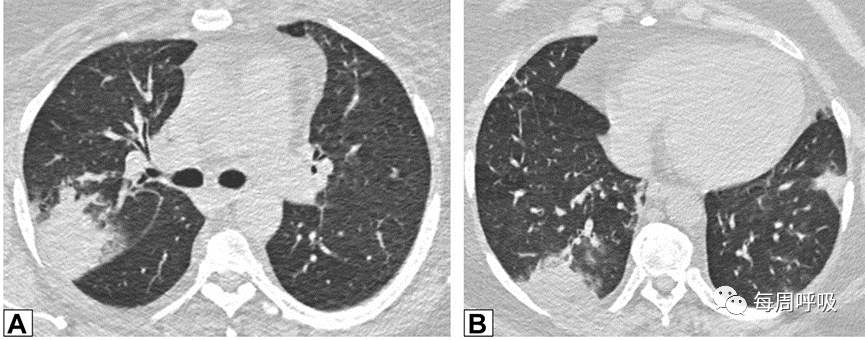

当以线性或网状为主的OP进一步发展,在周围实变或GGO后,基底和胸膜下网状形成,提示间质纤维化的发展(图17)。尽管蜂窝状和结构扭曲的发展可能表明纤维化的进展,OP也可在UIP或IPF中看到,使最终诊断复杂化。此外,OP可导致广泛的双基底牵引性支气管扩张,与背侧胸膜下肺区相对保留相关,其结果与非特异性间质性肺炎(NSIP)相似,并经常重叠(图18,图19)。

图17 间质纤维化。一名73岁男性在呼吸困难发作4天后获得的轴位CT扫描图像分别在隆突水平(A)和(C)以及肺基底水平(B)和(D)获得胸部CT扫描图像。上一排2019年的增强图像(A和B)显示双侧广泛的磨玻璃影(GGO)。2021年的图像(C和D)显示GGO程度改善,但出现网状和牵拉性支气管扩张或细支气管扩张,这一模式与纤维化相符。右肺上、中、下叶的楔形活检结果显示机化性肺炎。

图18非特异性间质性肺炎(NSIP)。51岁女性皮肌炎患者行CT平扫。通过下肺基底的轴位(A)和矢状位(B)图像显示双肺下叶实变,双侧胸膜下和磨玻璃。矢状位图像上支气管明显扩张(B)。这些表现与机化性肺炎和NSIP重叠一致。